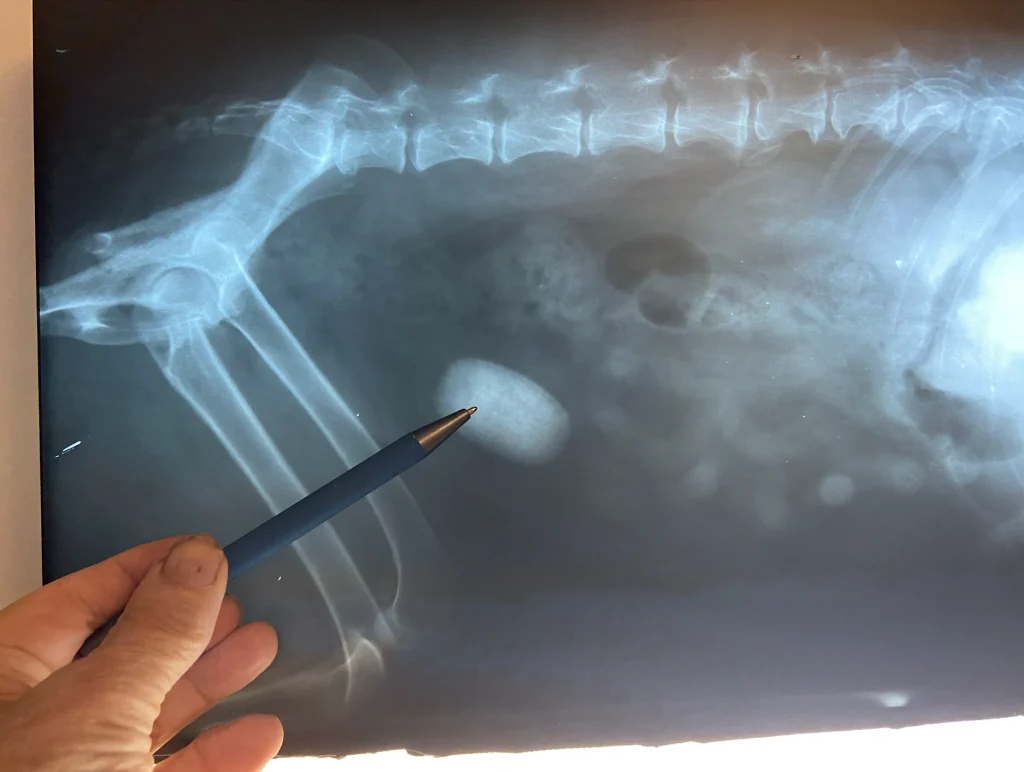

Understanding the basics of cat X rays helps pet owners grasp why this test matters. X rays provide a clear picture of a cat’s bones and organs. This imaging tool helps veterinarians find problems that are not visible outside.

Cat X rays show detailed images inside the body. They reveal broken bones, tumors, or fluid in the chest or abdomen. X rays also help check the heart size and lung condition.

Veterinarians use X rays to:

• Diagnose injuries from accidents or falls

• Detect bone diseases or fractures

• Find foreign objects swallowed by the cat

• Monitor chronic health issues like arthritis

• Guide treatment plans for internal problems